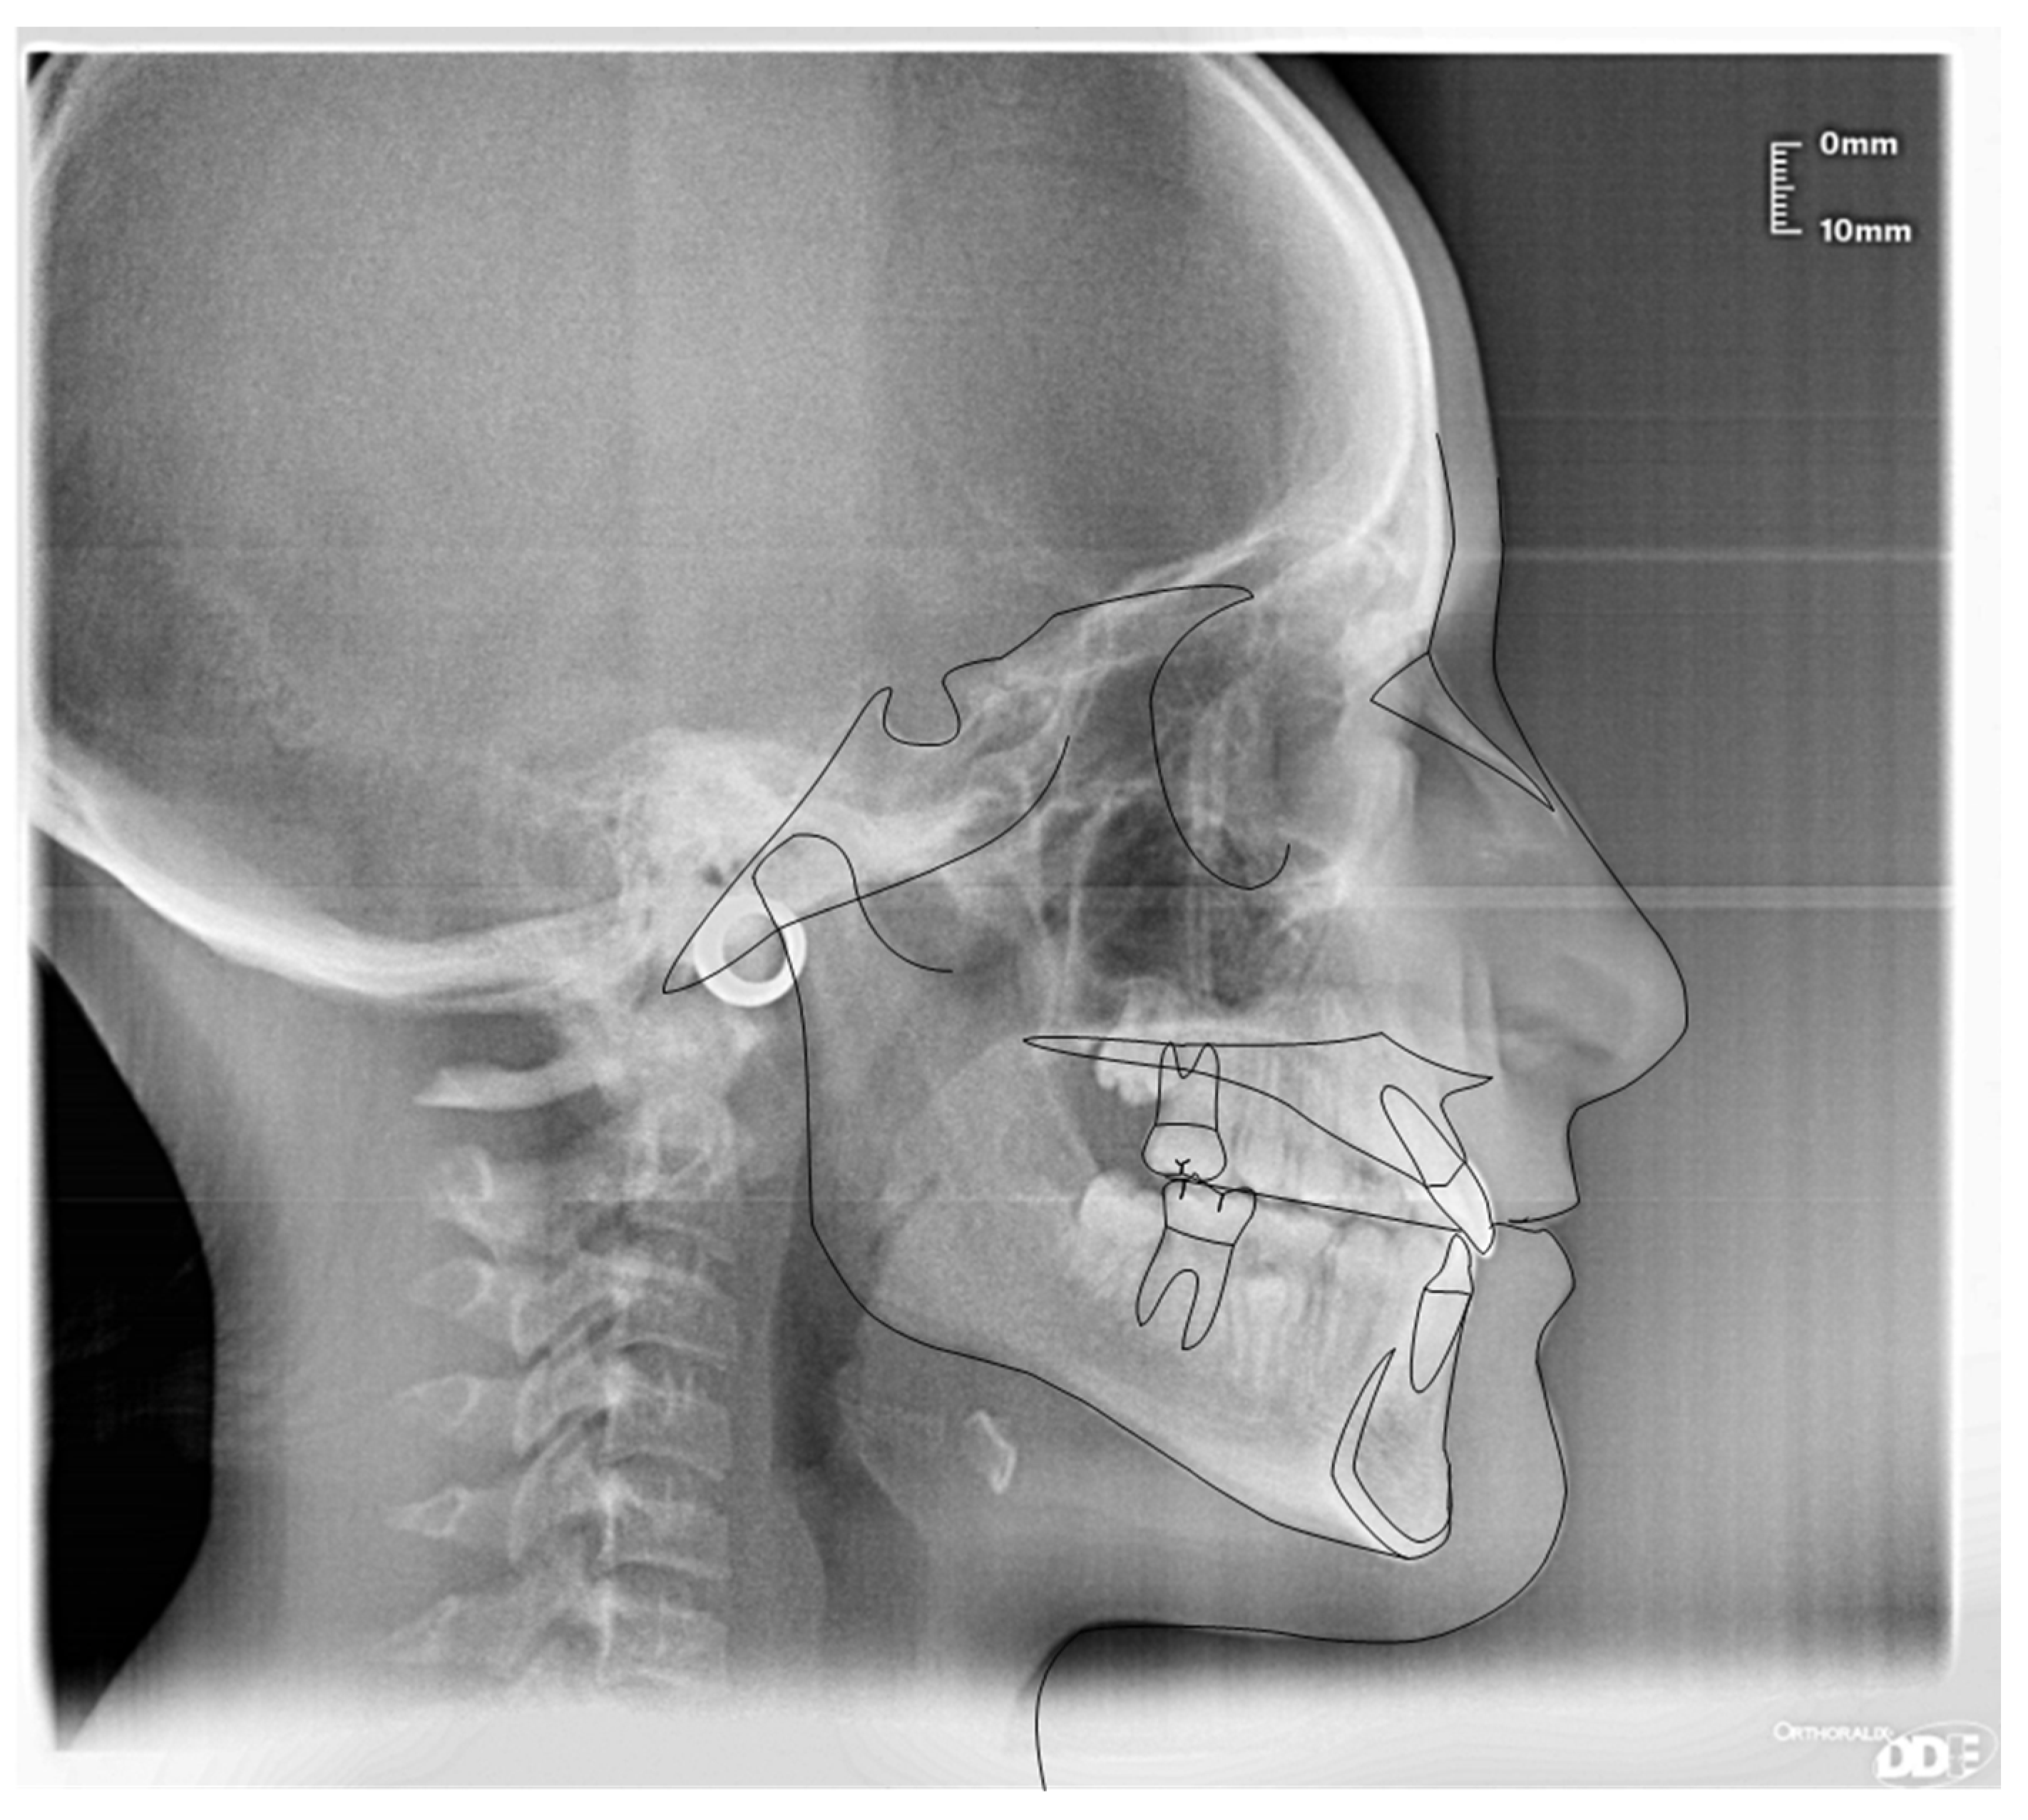

3.1. Clinical Case #1

3.2. Clinical Case #2

3.3. Clinical Case #3

3.4. Clinical Case #4